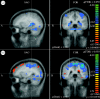

Thirty-one subjects have been included in the analysis (17 sham, 14 PELFMF; see table 1 for summary subject information). Differences were observed within groups over time, as well as between groups in functionally relevant areas: the anterior cingulate, the insula and the hippocampus/caudate (figures 2–4). For each figure, the blue/green false colours indicate that there was less activation in the post-exposure (PELFMF or sham) compared with the pre-exposure fMRI, and the yellow/red colours indicate more activation during the painful stimulus after exposure compared with pre-exposure.

Anterior cingulate. (a) PELFMF post- to pre-condition. This is the statistical difference between the activation seen with pain after exposure minus that seen before. There was a significant decrease in activity after PELFMF exposure compared with before …

Ipsilateral insula. (a) PELFMF post- to pre-condition. This image shows a significant decrease in activity within the right insula following PELFMF exposure when compared with pre-exposure. (b) Sham post- to pre-condition. No difference is seen due to …

Hippocampus/caudate. (a) PELFMF post- to pre-condition. This image shows a significant decrease in activity within the hippocampus/caudate area following PELFMF exposure when compared with pre-exposure. Due to the relatively poor spatial resolution, it …